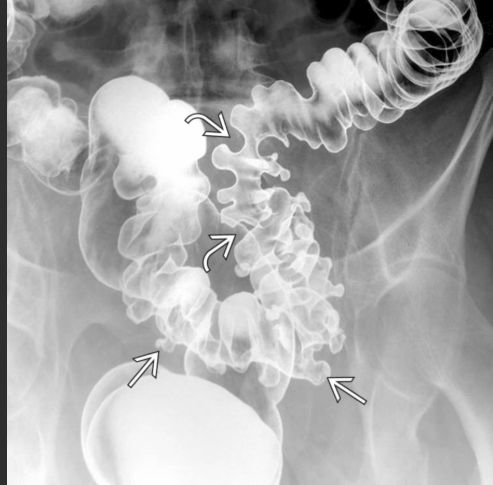

A maioria dos pacientes com diverticulose tem doença no cólon ______(direito/esquerdo), porém a do cólon _______(direito/esquerdo) é frequente em pacientes asiáticos (43%-50%).

Esquerdo; direito.

Diverticulose cólica (seta reta). Hipertrofia da camada muscular (seta curva)